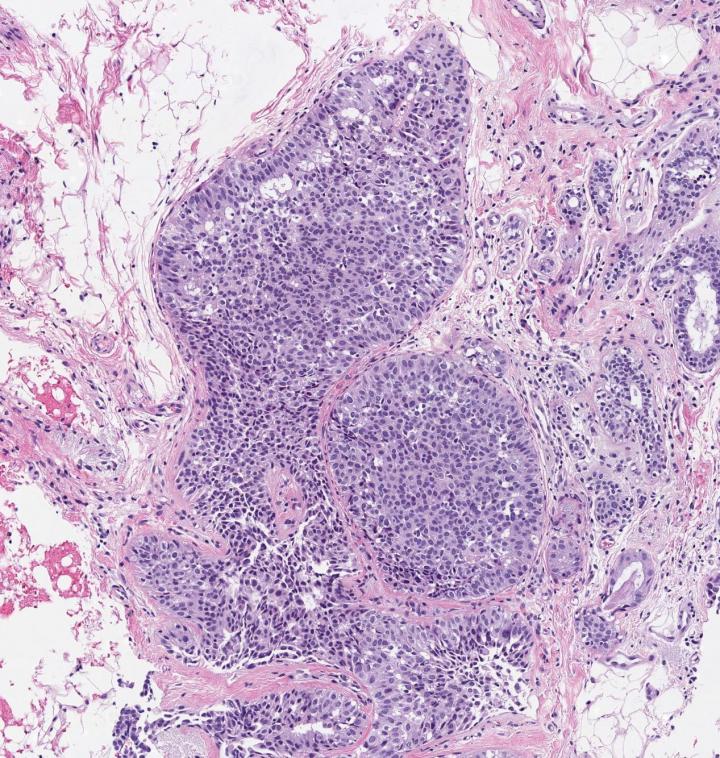

image: A microscopic image of breast tissue showing proliferative benign breast disease, including abnormal cells

They also classified the BBDs as non-proliferative or proliferative, depending on whether or not the breast tissue showed an increase in the growth of certain cells, such as the ductal cells found in ductal hyperplasia in which there is an overgrowth of cells lining the ducts inside the breast.